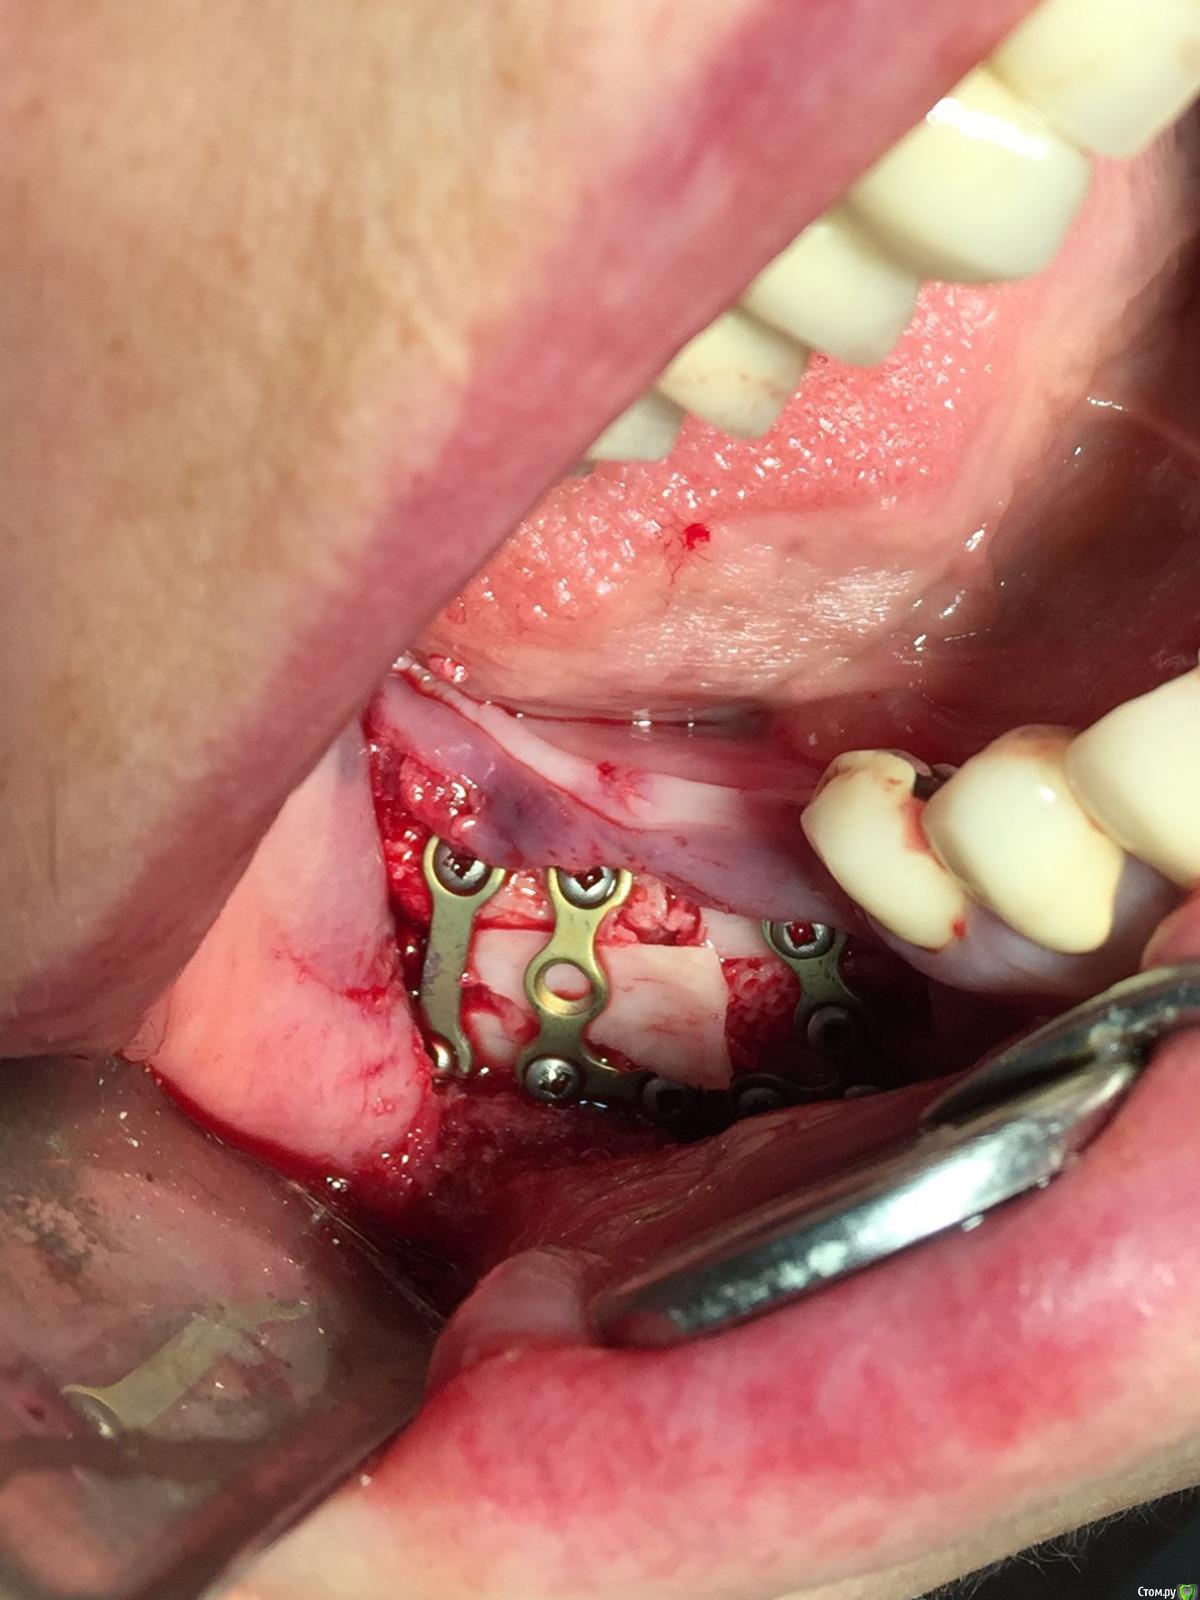

Evikrol Опубликовано 23 октября, 2015 Поделиться Опубликовано 23 октября, 2015 Чем распилы проводили? И что за блок? Ссылка на комментарий

diesel87 Опубликовано 23 октября, 2015 Поделиться Опубликовано 23 октября, 2015 Чем распилы проводили? И что за блок?Китайский пьезо, блок от Остеобиола) Ссылка на комментарий